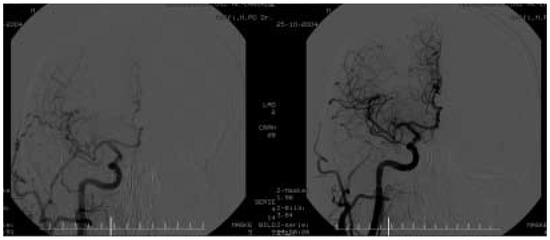

Die Behandlung der Karotisstenose: Die Sicht des Mikroneurochirurgen

by Luigi Mariani and Alain Barth

Cardiovasc. Med. 2005, 8(9), 315; https://doi.org/10.4414/cvm.2005.01119 - 30 Sep 2005

Viewed by 108

Abstract

According to the large, randomised, multicentric trials of the 1990’s, carotid-endarterectomy (CEA) is the «gold standard» of treatment for most patients with a proximal stenosis of the internal carotid artery (ACI), especially for those with a high-grade (70–99%), symptomatic stenosis. During the last [...] Read more.

According to the large, randomised, multicentric trials of the 1990’s, carotid-endarterectomy (CEA) is the «gold standard» of treatment for most patients with a proximal stenosis of the internal carotid artery (ACI), especially for those with a high-grade (70–99%), symptomatic stenosis. During the last years CEA has been further refined and standardised. Its results in terms of stroke risk and mortality are so good, that CEAcan be recommended as the prophylactic treatment of choice even in patients with an asymptomatic, highgrade ACI-stenosis and in patients with a 50–69%, evidently symptomatic stenosis, provided that their approximate life expectancy exceeds five years. Today’s scientific evidence, the current results of CEA, but also the analysis of the relevant, known pro’s and con’s of CEA and of the current endovascular treatment options, e.g. carotid angioplasty and stenting (CAS) support the view of CEA being the first option for ACI-stenosis. Full article

Show Figures

Figure 1